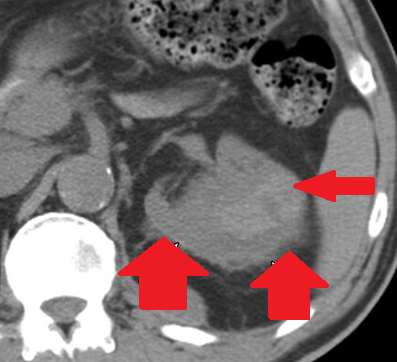

Αυτόματη ρήξη/αιμορραγία νεφρού — αγγειομυολίπωμα (Ευγενική παραχώρηση Dr. V. Penopoulos)